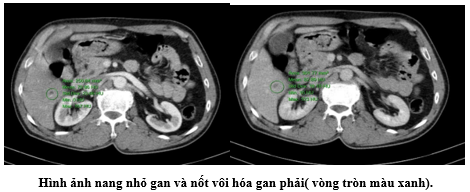

- Chụp CT ổ bụng: Nốt vôi hóa gan phải đường kính 5mm, gan có vài nang, đường kính lớn nhất 9mm.